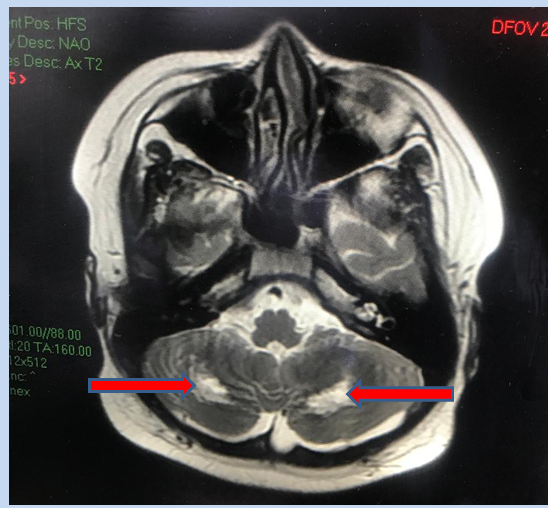

Xét nghiệm thấy phản ứng viêm trong máu tăng cao trở lại. Còn MRI não ghi nhận tổn thương đồi thị hai bên, tổn thương chất trắng của tiểu não. Bác sĩ chẩn đoán, bệnh nhi bị hội chứng viêm đa hệ thống, tổn thương não. H. được điều trị kháng viêm liều cao, kháng đông phòng ngừa tắc mạch.